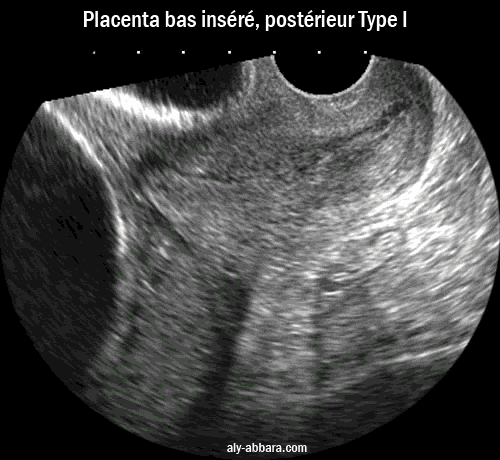

Placenta prævia, postérieur

(Type I selon BESSIS R, BRIGNON C, SCHNEIDER L. 1976)

à 36 semaines d'aménorrhée

Cette image montre l'insertion anormale du placenta ; il s'insère sur la paroi postérieure du segment inférieur,

mais il ne recouvre pas l'orifice interne du col utérin ; la distance qui le sépare de cet orifice est de 12 mm.

Placenta postérieur bas inséré, type I